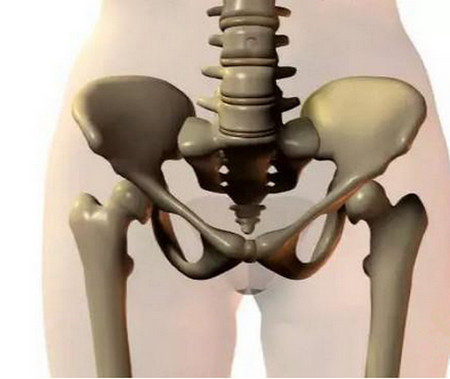

骨盆

骨盆也就是胎儿出生的过道,通俗点讲就是所谓的产道。骨盆的直径比较短,入口比较宽的话就比较容易的顺产。

因为直径短入口比较宽的话,腹中的胎儿就比较容易的临盆,分娩的过程就会比较的顺利。如果盆口比较窄的话,就不容易顺产。孕妈在产前产科医生都会测量骨盆入口和出口的大小,发现不能顺产的一般都会产区剖腹产。